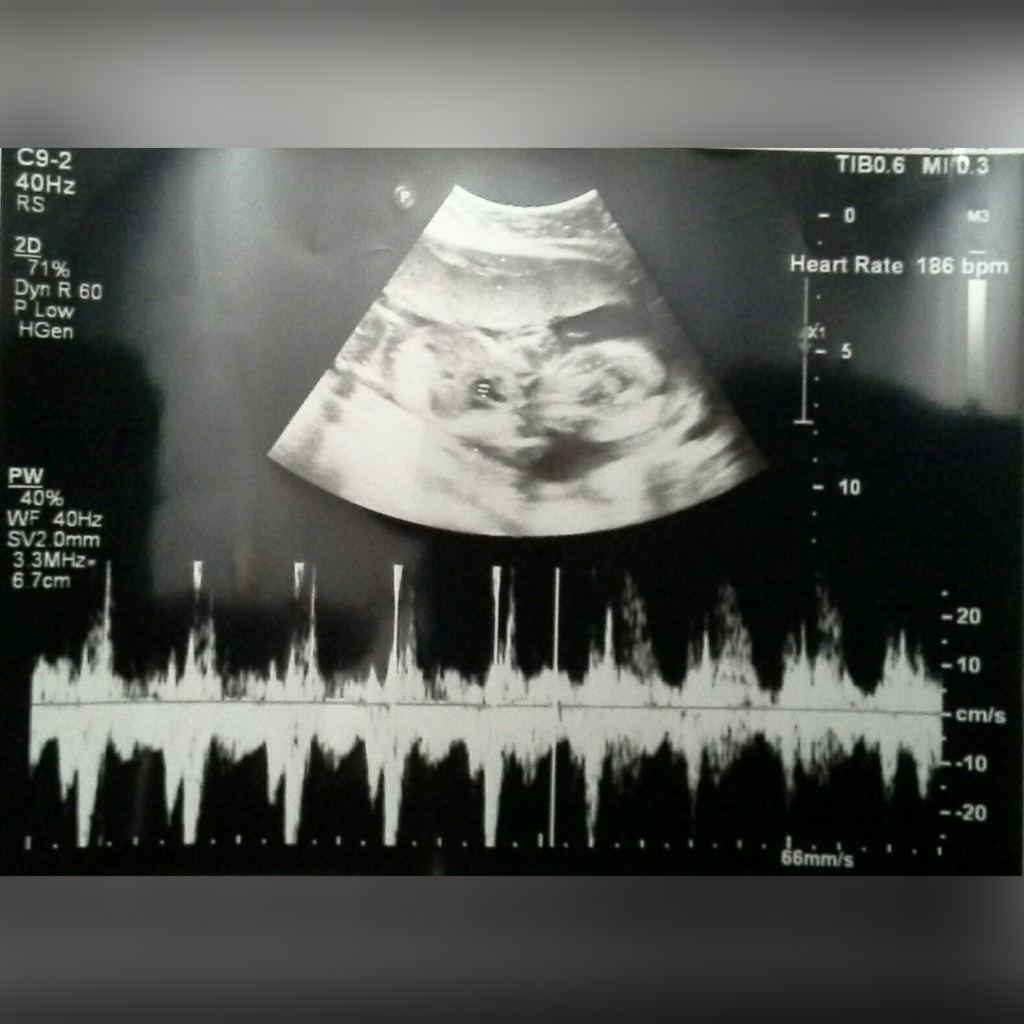

Siang hari nya, setelah konsultasi lewat WA sama dokter,  si adek langsung usg seperti biasa..

Kata dokter, detak jantung, dan lain - lain nya baik - baik aja..

Tapi, buat lebih meyakinkan pemeriksaan, aku diminta buat NST (Non Stress Testing), yaitu tes buat melihat detak jantung, gerakan janin, sama kontraksi rahim..

Alatnya mirip - mirip semacam usg gitu, cuman layar nya lebih kecil, isinya cuma angka sama grafik..

Sekali NST kira-kira butuh waktu sekitar 15 menit..

Si adek 31 minggu